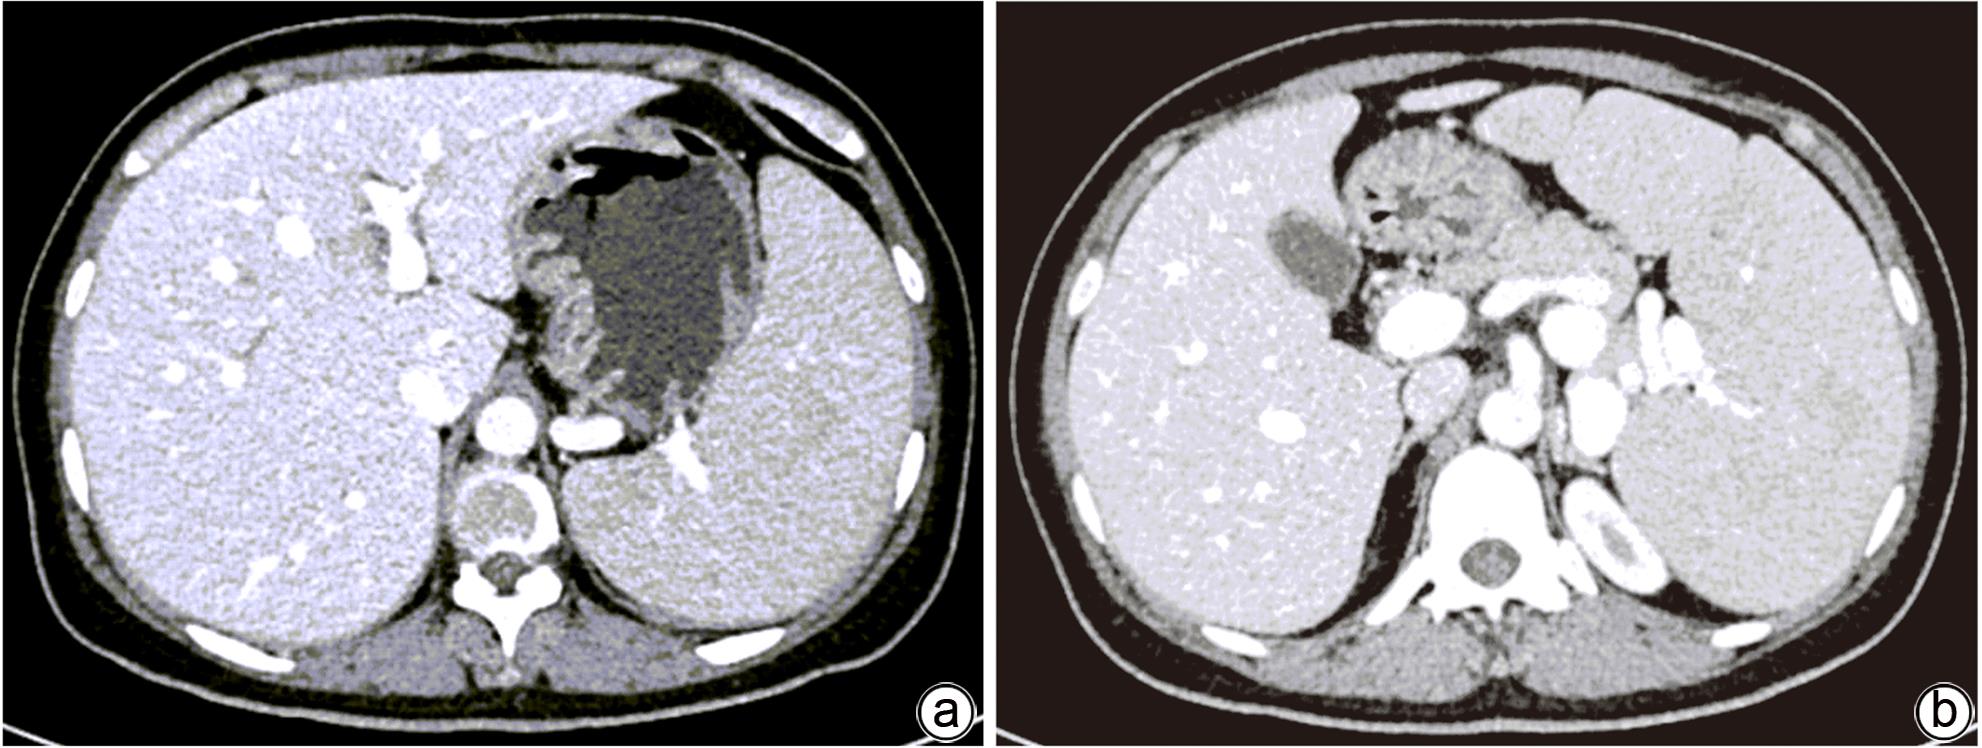

Misdiagnosis of intrapancreatic accessory spleen: A report of two cases

Mengzhe ZHANG, Jie RAO, Zhengle ZHANG

2024, 40(2): 365-368. DOI: 10.12449/JCH240223

Abstract(1384) HTML (333) PDF (1188KB)(176)

Abstract:

Accessory spleen refers to the spleen tissue that exists outside of the normal spleen, with a similar structure to the main spleen and certain functions. Intrapancreatic accessory spleen (IPAS) completely enveloped by the pancreas has an incidence rate of only 2%, and it is easily misdiagnosed in clinical practice due to its atypical clinical symptoms and similar radiological features to pancreatic neuroendocrine tumor, pancreatic solid pseudopapillary tumor, and other pancreatic space-occupying lesions. This article reports the clinical data of two patients with IPAS who were misdiagnosed as pancreatic neuroendocrine tumor and pancreatic solid pseudopapillary tumor, respectively, analyzes the reasons for misdiagnosis, and summarizes the experience in diagnosis and treatment, in order to improve the ability for the differential diagnosis of IPAS in clinical practice.